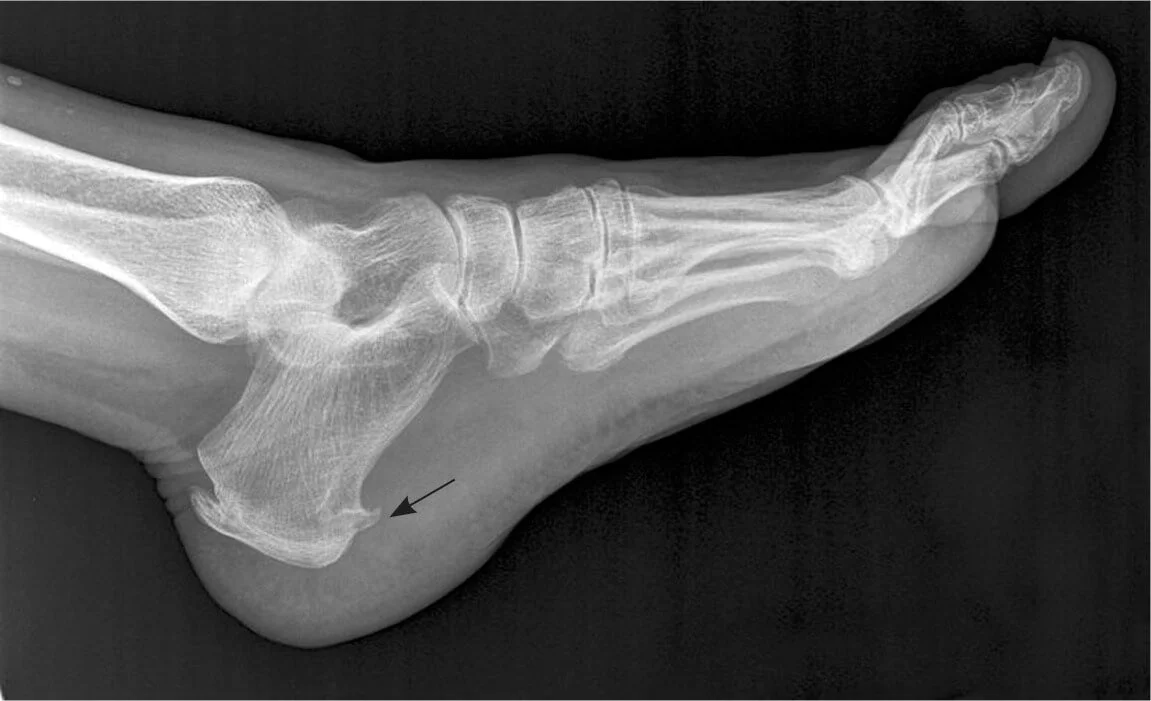

Imaging studies, like X-rays, aren't always necessary but can be useful in ruling out other conditions, such as stress fractures that might be confused with plantar fasciitis.

When experiencing heel and arch pain, you might be referred for an X-ray to rule out certain conditions. Sometimes, the results reveal a heel spur, which can mislead your plantar fasciitis treatment.

A heel spur sounds like a plausible cause of foot pain—after all, it conjures images of a sharp spike digging into your heel. However, finding a heel spur on a scan is often incidental, meaning it likely has nothing to do with your discomfort. Heel spurs are brittle calcifications of the plantar fascia—imagine stepping on a crispy potato chip rather than a solid spike.

Interestingly, heel spurs are present in up to 20% of the population, not just the 1% experiencing plantar fasciitis. This indicates that heel spurs do not necessarily equal pain.